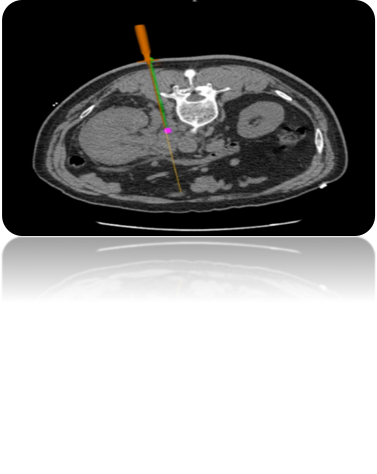

運用介入穿刺診療系統(tǒng):通過接受的坐標信息與CT圖像融合重建3D模型,幫助醫(yī)生尋找病灶點、提供精準穿刺路徑規(guī)劃和實時導航;利用磁場發(fā)生器:實時接收來自定位貼片和定位針的信號,反饋到診療系統(tǒng)內(nèi)。

2:路徑規(guī)劃:導入CT圖像后,根據(jù)算法迅速重建3D模型,精準尋找病灶點及入針點;

4:術(shù)中實時導航:導航針在病人體內(nèi)實時反饋位置,給與醫(yī)生進針方向指導。